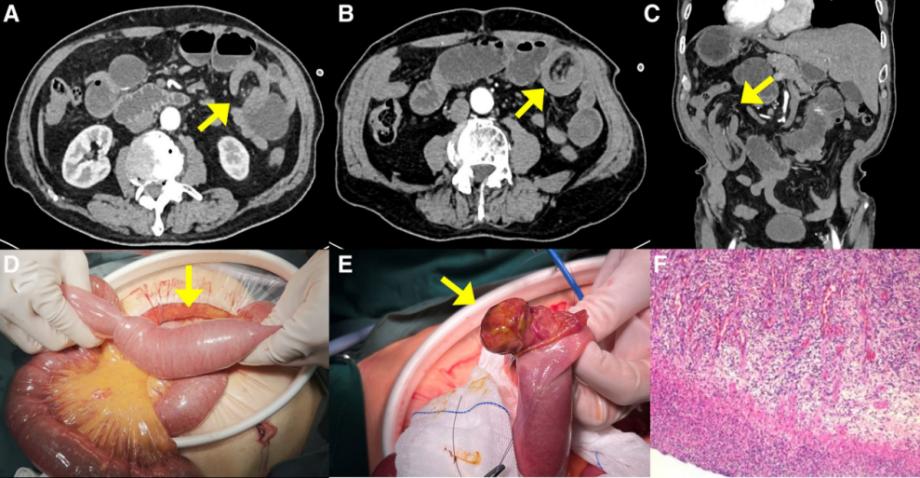

患者81岁,中国男性,有7天的间歇性左腹痛病史,伴有恶心和呕吐。入院前两天最后一次排便和排气。腹部计算机断层扫描(CT)显示左上腹小肠梗阻,一段小肠系膜插入另一段,肠套叠的可能性很高(图1A-C)。随后,患者在手术室接受了剖腹手术,在距离Treitz韧带60厘米处发现了由2.5厘米×3.5厘米息肉样肿瘤引起的空肠段肠套叠(图1D和E)。患者接受了部分肠手术切除,手术在2小时内完成,估计失血量约为30毫升。患者恢复顺利,术后1周出院。术后对患者进行了2年的密切随访,包括随访腹部CT扫描,未发现复发迹象。

图1.:(A-F)病例1的围手术期放射学特征、术中表现和术后组织病理学特征。(A、B、C)腹部CT显示肠套叠的“靶征”和“杯状征”(黄色箭头)。(D) 手术探查显示,肠的近端部分及其肠系膜进入更远端的部分。(E) 观察到3.5 cm×2.5 cm的病变(黄色箭头)。(F) 显微镜检查显示,病变侵犯了固有肌层,并观察到含有嗜酸性粒细胞的炎性细胞背景。CT=计算机断层扫描

病理检查显示息肉样肿物侵犯了固有肌层。肠黏膜被侵蚀,下方形成肉芽组织,血管丰富,血管周围可见散在分布的粗大异形囊肿,核仁明显,可见核分裂,细胞质丰富(图1F)。免疫组织化学显示,异形细胞对ALK、Ki-67和B-Catenin呈阳性,对HMB45、CD117、CD34、SMA、Desmin、DOG1、CD31和ERG呈阴性。结合免疫组化染色,梭形细胞对CD34呈弱阳性,对Ki-67呈阳性,对STAT6、DOG-1、AE1/AE3、ALK(Ventana-D5F3)、GFAP、S-100、SOX10呈阴性。粘膜下层可见增殖的间充质细胞,呈梭形和星状,伴有嗜酸性浸润,与IFP一致。